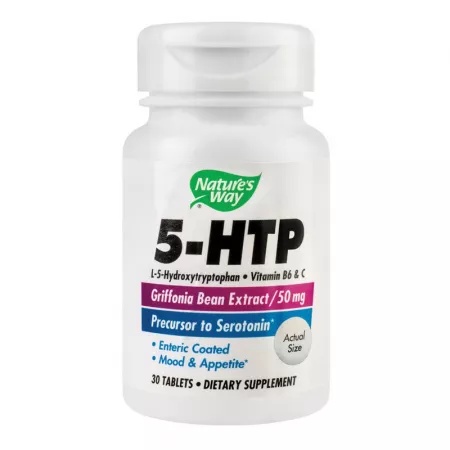

5 HTP 100, 60 capsule, Herbagetica

184,82 lei5-HTP Nature’s Way, 30 tablete, Secom

218,95 lei5-HTP, 30 capsule, Adams

79,73 lei5-HTP, 30 capsule, Solgar